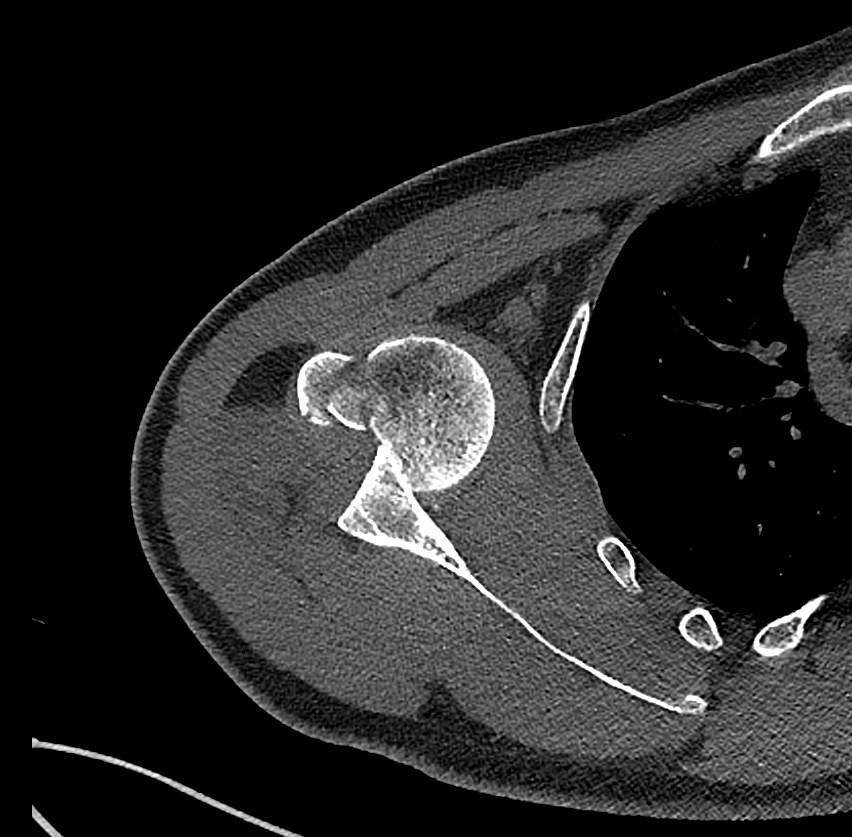

Hydatid disease is a parasitic disease caused by Echinococcosis Granulosus, which may affect the whole body. It most often spreads to the liver and lungs (1,2). Radiological imaging and serological testing are generally used diagnostic techniques. Ultrasonography is the first choice in radiological imaging for the diagnosis of hydatid cyst. However, CT and MRI can be used for differential diagnosis or in classification. Ultrasonography images of hydatid cysts vary according to the stage of maturation (3).

Gharbi classified hydatid cyst ultrasonographic images into 5 types: Type 1, walled, unilocular, anechoic; type 2, separated membranes; type 3, multisepta, daughter vesicles; type 4, heterogenic, hypo-hyperechogenic; type 5, calcification of a section of the wall or completely calcified (4). The cysts characteristically have three components: Pericyst, Exocyst, and Endocyst.